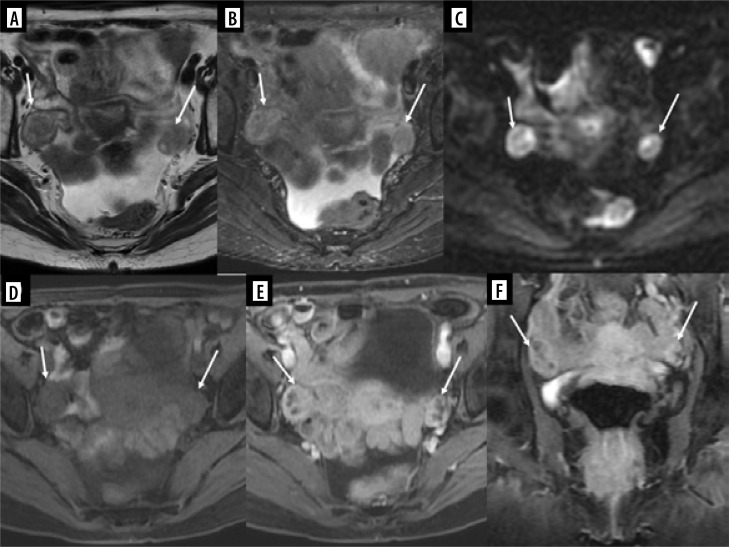

报告了四例软组织或骨肉瘤转移到生殖系统或乳房的女孩病例。其中两名患者的四肢横纹肌肉瘤(RMS)转移至乳房,一名患者的足部横纹肌肉瘤转移至卵巢,一名患者的骶骨软骨肉瘤转移至子宫静脉丛。在每个病例中,转移灶的外观都通过不同的成像方法显示出来:超声波、磁共振成像和计算机断层扫描。全面的文献回顾证实,只有少数病例描述过女孩软组织和骨肉瘤转移到本文主要关注的部位,尤其是生殖器官。尽管这种类型的转移很少发生,但在区分来源时,仍应考虑上述恶性肿瘤。这些罕见的临床情况被编织成一篇关于恶性肿瘤转移到生殖器官和乳房的综述。

Four cases of girls with metastases of soft tissue or bone sarcomas to the reproductive system or breasts are reported. Two patients had metastases to the breast from rhabdomyosarcoma (RMS) of the limbs, one had metastases to the ovary from RMS of the foot, and one had metastases to the uterine venous plexus from chondrosarcoma of the sacrum. In each case, the appearance of metastases was shown in various imaging methods: ultrasound, magnetic resonance imaging, and computed tomography. A thorough literature review confirmed that only a few cases of soft tissue and bone sarcoma metastasis to the locations of primary interest of this article in girls have been described, especially in the context of reproductive organs. Despite the rare occurrence of this type of metastases, the malignant tumours mentioned above should be considered when differentiating the source. These rare clinical situations are woven into a review of malignant neoplasms' metastases to the reproductive organs and breast.